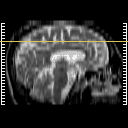

Click on sagittal image to select slice. Click on thin tickmark to change timepoint, or thick tickmark for overlay.